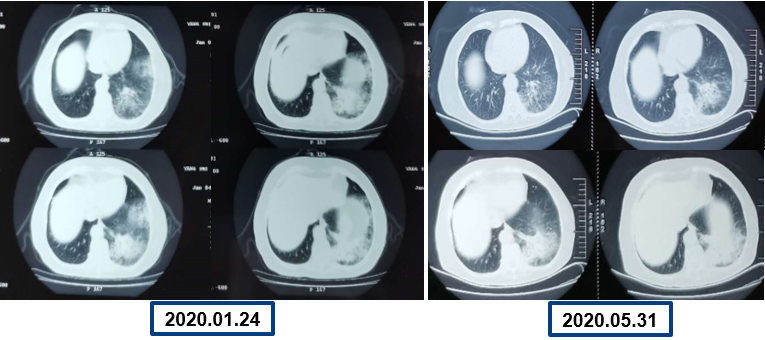

为提升肺癌前线免疫联合抗血管治疗的诊疗观念,学习与追踪肺癌领域诊疗最前沿知识,充分交流免疫/抗血管用药不良反应管理临床经验,【An例说】肺癌病例项目,征集大量临床高质量免疫联合抗血管治疗肺癌病例,并邀请全国各区域中青年及高职称医生与顶级TOP KOL互动发声!通过理念结合实践,研究结合病例,线上联动,共同促进学术由KOL/ROL向中青年医生下沉,为提升我国肺癌诊疗整体水平势在必行。免疫治疗的出现,对于晚期肺癌患者而言,显著提高了患者的生存质量及延长生存期,多项研究表明免疫治疗对于PD-L1表达阴性的患者也具有一定的治疗效果。为此,上海长海医院(海军军医大学第一附属医院)团队为您带来一例肺癌免疫联合抗血管病例分享。 患者,女性,78岁 2017年体检时发现左下肺结节,未行诊断及治疗。 2018.11.21、2019.09.24胸部CT均提示病灶较前变大,仍未诊治。 影像学检查 2020.01初逐渐出现胸闷、气短,活动后尤为明显。多次就诊于当地医院输液治疗(具体不详)。入院前2周胸闷,气急症状加重,无发热,无明显咳嗽,咳痰。2020.06.23入院。 影像学检查 既往史:高血压病30余年,最高血压170/90mmHg,规律服用美托洛尔12.5mg+利血平 0.1mg/日,自诉血压控制可。 个人史:无特殊 婚育史:无特殊 家族史:无特殊 T:37.0℃ P:104次/分 R:30次/分 BP:134/58mmHg 右肺及左肺可闻及湿罗音,左下肺呼吸音弱,无胸膜摩擦音。 心脏查体无异常。 入院后 CT引导下肺穿刺 穿刺后无咳嗽咯血,胸闷气急症状无加重。 6.25 出院等病理。 自行口服易瑞沙治疗,家中持续吸氧。 出院后3天突发病情变化: 6.28 凌晨1点左右,如厕后出现呼吸困难加重,晕倒。家属约2点发现,送至急诊,急诊予化痰、平喘、抗感染等对症治疗。 影像学检查 急诊检验检查: 【血气分析】PH 7.35、PO2 45.9mmHg、PCO2 62.6mmHg 【BNP】23.38pg/ml;【D-二聚体】0.32 【血常规】WBC:9.23×109/L、RBC:3.58×1012/L、HGB:98g/L、N%:80.2%、PLT:203×109/L。 【炎症指标】CRP:2.95mg/L;ESR:4mm/H;PCT:0.045ng/ml 【心电图】1. 窦性心动过速、2. ST-T异常。 血气分析 2020.06.29再次入院:左下肺腺癌、Ⅱ型呼吸衰竭、右肺阴影待查。 右肺渗出原因分析:感染?肿瘤进展?药物相关? 血常规变化: 选择治疗方案: 1. 两肺炎症,纵隔稍大淋巴结,炎症较2020.6.24进展,建议抗炎治疗后复查; 2. 左侧胸腔少许积液; 3. 两肺肺气肿、肺大泡,右肺中叶钙化灶; 4. 右侧第4肋骨皮质扭曲,请结合临床; 5. 甲状腺两侧结节,请结合超声。 右下肺腺癌 PD-L1无表达 抗血管生成与免疫联合的优点: 1、抗血管生成,靶点全面、强效抑制 2、抑制肿瘤细胞增殖和迁移,重塑肿瘤微环境,联合增效 3、肿瘤血管正常化及重塑,减轻免疫抑制状态 4、增加免疫效应细胞浸润 5、免疫刺激作用,激活免疫效应细胞 信迪利单抗联合安罗替尼的临床研究:这是一项前瞻性、非随机、三臂、Ib期临床研究。 临床研究试验设计 临床研究PFS和OS曲线 安罗替尼联合信迪利单抗一线治疗NSCLC,ORR达72.7%,DCR达100%,mPFS=15.6m,24m,OS率83.9%,表现出良好的治疗潜力。 派安普利单抗联合安罗替尼的临床研究:随机、双盲、多中心III期临床研究(NCT03866980) 临床研究试验设计 安尼可联合安罗疗效的ORR和DCR分析 数据截止日期:2021.1.13,共26例患者入组安尼可联合安罗替尼组,21例患者至少完成一次疗效评价。 帕博利珠单抗+安罗替尼 8mg。 治疗过程影像学检查 疗效评估: 2021.08.03: 疗效评估PR,截止目前PFS=15m。 该病例采用PD-L1抑制剂帕博利珠单抗联合小分子多靶点抗血管生成药物安罗替尼治疗老年肺腺癌患者,获得了15个月的PFS,提示对于驱动基因阴性,PD-L1无表达的晚期非小细胞肺癌患者免疫联合抗血管生成药物治疗是NSCLC患者一线治疗的选择和手段之一。 Impower150研究显示,贝伐珠单抗联合PD-L1抑制剂阿替利珠单抗+化疗显著改善了无突变非鳞NSCLC患者的PFS,中位OS达19.4个月(对照组14.7个月),ORR为71%。但治疗相关的毒副反应较大,一定程度上影响患者生活质量。小分子TKI联合免疫作为肿瘤去化疗联合治疗模式,越来越受到关注,前期探索性前瞻性随机临床研究包括信迪利单抗+安罗替尼(ACTION研究)、派安普利单抗+安罗替尼(AK105-301研究)和卡瑞利珠单抗+Apatinib/ target=_blank class=infotextkey>阿帕替尼(SHR-1210-III-315 研究)等一线治疗驱动基因阴性晚期NSCLC均得到了较好结果, 信迪利单抗联合安罗替尼组ORR达72%,DCR100%,中位PFS15.6个月,2年OS率83.9%,耐受性良好,显示出多靶点抗血管生成药物联合的良好应用前景。 免疫与抗血管生成药物以及与其他药物或方式联合该如何排兵布阵,肺癌治疗如何真正践行个体化和精准化,还有许多问题和挑战,有待进一步研究拓展和证实。 病例分享 焦洋 教授 上海长海医院,副主任医师,副教授 海军军医大学长海医院呼吸与危重症医学科 美国田纳西州大学附属医院呼吸与危重症医学科访问学者 上海市医学会呼吸分会感染学组秘书 中国老年医学会感染诊治与合理用药学术委员会委员 专业方向:疑难、复杂肺部感染及呼吸危重症的救治,肺癌的早期诊断和治疗。 专家点评 韩一平 教授 海军军医大学第一附属医院 呼吸与危重症医学科教授、主任医师 博士生导师 海军军医大学第一附属医院临床教育中心主任 中华医学会呼吸分会肺癌学组委员 中国医药教育协会肺部肿瘤专委会常委 中国医师协会全科分会委员,上海全科分会副会长 《中国肿瘤生物治疗杂志》《中国全科医学杂志》 《第二军医大学学报》《内科年鉴》等编委 获校“特级优秀教师”,上海市“育才奖” 首届上海“最美女医生” 主编发表教材或专著5部,近年发表文论50余篇 *仅供医学药学专业人士阅读 文章来源:ONCO前沿案例详情